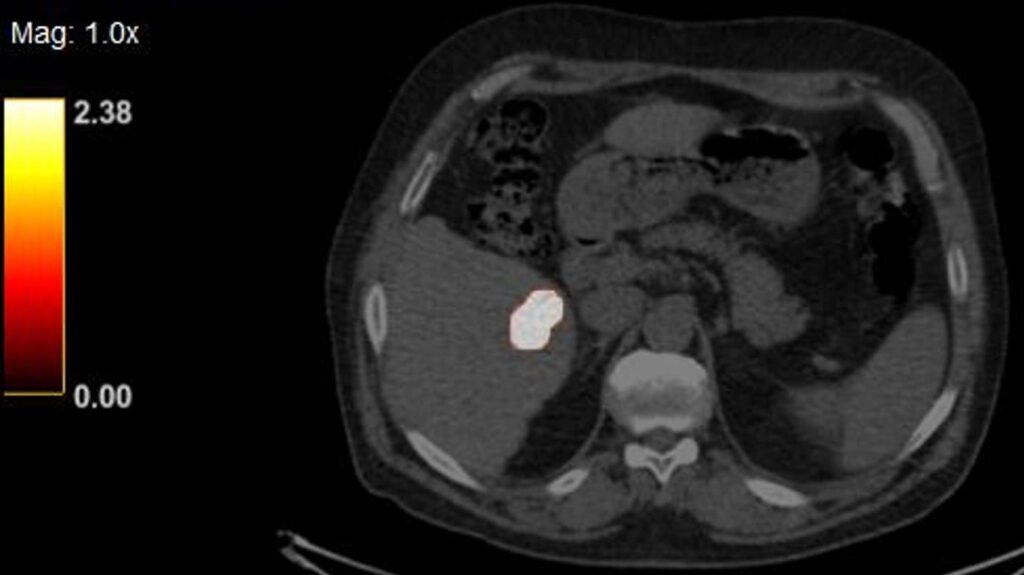

• YntraDose (previously called BAT-90) has been studied in a FIH Trial to assess the performance of BAT-90 during the percutaneous ablative procedure of resectable and unresectable primary liver lesions (HCC).

The study indicated that No treatment related AEs and ADEs limiting the ability to deploy YntraDose occurred and 100% of the lesions treated showed to have been reached by the product.